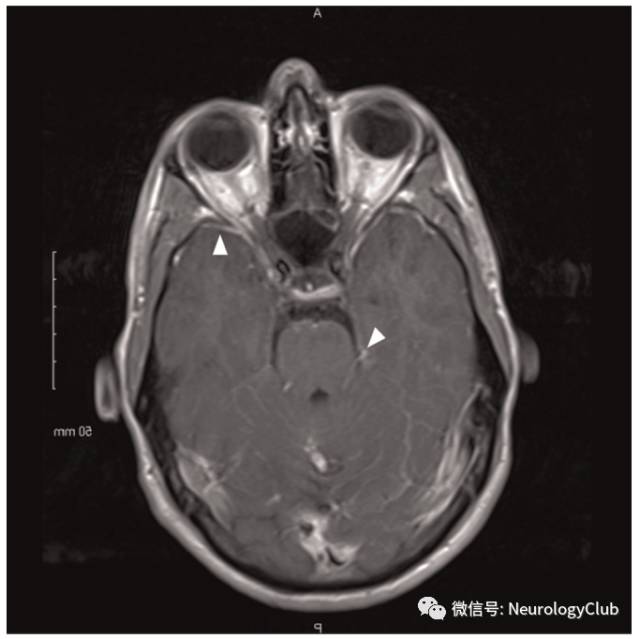

(图26:头颅MRI可见位于右侧小脑上脚和中脑的动脉瘤,伴脑干弥漫高信号;DSA证实为右侧小脑上动脉动脉瘤)